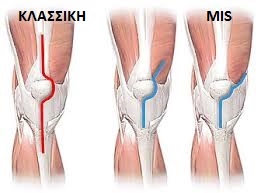

Η χρήση ελάχιστης παρεμβατικότητας MIS μεθόδων, έχει στόχο να μειώσει το χειρουργικό τραύμα. Όταν χρησιμοποιούμε τον όρο αυτό στην ολική αρθροπλαστική γόνατος εννοούμε κατά βάση την τροποποίηση της χειρουργικής προσπέλασης. Προσπέλαση είναι ο «δρόμος» που ακολουθεί ο χειρουργός για να φτάσει από το δέρμα μέχρι το οστό. Στο γόνατο, αυτό είναι κριτικής σημασίας. Έχει αποδειχθεί ότι όσο λιγότερο παρεμβαίνει κανείς στο φάκελο που περιβάλλει την άρθρωση, τόσο λιγότερο πόνο θα βιώσει ο ασθενής μετά την επέμβαση Αρθροπλαστικής Γόνατος. Ομοίως, τόσο λιγότερη αντίσταση θα προβάλει το γόνατο στη μετεγχειρητική αποκατάσταση. Στην κλασσική αρθροπλαστική, η πρόσβαση στην Άρθρωση γίνεται μέσω μεγάλων τομών 25-30 εκατοστά – ακολουθεί διατομή του εκτατικού μηχανισμού, πιο συγκεκριμένα του τένοντα του τετρακεφάλου. (εικόνα 7 ). Αυτό αποτελεί έναν σημαντικό τραυματισμό με αρνητικές επιπτώσεις στην προσπάθειά μας να αποκαταστήσουμε την κίνηση μετεγχειρητικά. Ο λόγος είναι ότι το γόνατο απαντά με επώδυνη μυϊκή σύσπαση.

Συνολικά, το αιμάτωμα και το οίδημα μετά αρθροπλαστική με μεγάλες αποκολλήσεις, είναι εκτεταμένα. Στην MIS φιλοσοφία, αντίθετα, η πρόσβαση γίνεται «σηκώνοντας» και όχι κόβοντας τους μύες και τένοντες στην πρόσθια επιφάνεια. Η προσπέλαση γίνεται σε επίπεδο πιο περιφερικά από τις μυοτενόντιες ομάδες.(εικόνα 7 ). Διεθνώς η προσπέλαση που χρησιμοποιούμε ονομάζεται «subvastus» και αφήνει άθικτο τον εκτατικό μηχανισμό. Όλη η διαδικασία δεν απαιτεί μεγάλες τομές. Αντίθετα, μπορεί να γίνει διαμέσου μικρών τομών με το μισό μήκος σε σύγκριση με την κλασσική προσέγγιση. (εικόνα 8 )